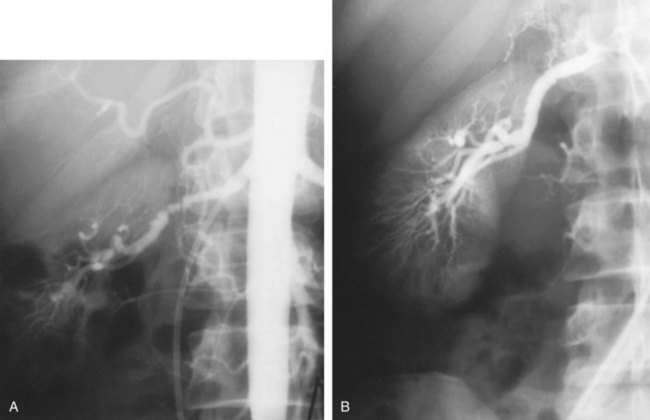

Angiography in primary intimal fibroplasia reveals a smooth, fairly focal stenosis, usually involving the proximal or midportion of the vessel or its branches (Fig. 39–3). Dissecting hematomas may distort the area of the stenosis. With nonoperative management, progressive renal artery obstruction and ischemic atrophy of the involved kidney invariably occur. Severe intimal fibroplasia may subsequently develop de novo in the contralateral renal artery. Although primary intimal fibroplasia most commonly affects the renal arteries, it may also occur as a generalized disorder with concomitant involvement of carotid, upper and lower extremity, and mesenteric vessels.

Medial fibroplasia is the most common of the fibrous lesions, constituting 75% to 80% of the total number. It tends to occur in women between the ages of 25 and 50 years and often involves both renal arteries. It may involve other vessels in the body, most notably the carotid, mesenteric, and iliac arteries. Microscopically, the internal elastic membrane is focally and variably thinned and lost. Within the alternating thickened areas, much of the muscle is replaced by collagen, hence the term medial fibroplasia. In other areas, thinning of the media occurs to the point of complete loss, and microaneurysms can be seen as saccules lined by only the external elastica. In extreme cases, giant aneurysms may be found in association with medial fibroplasia.